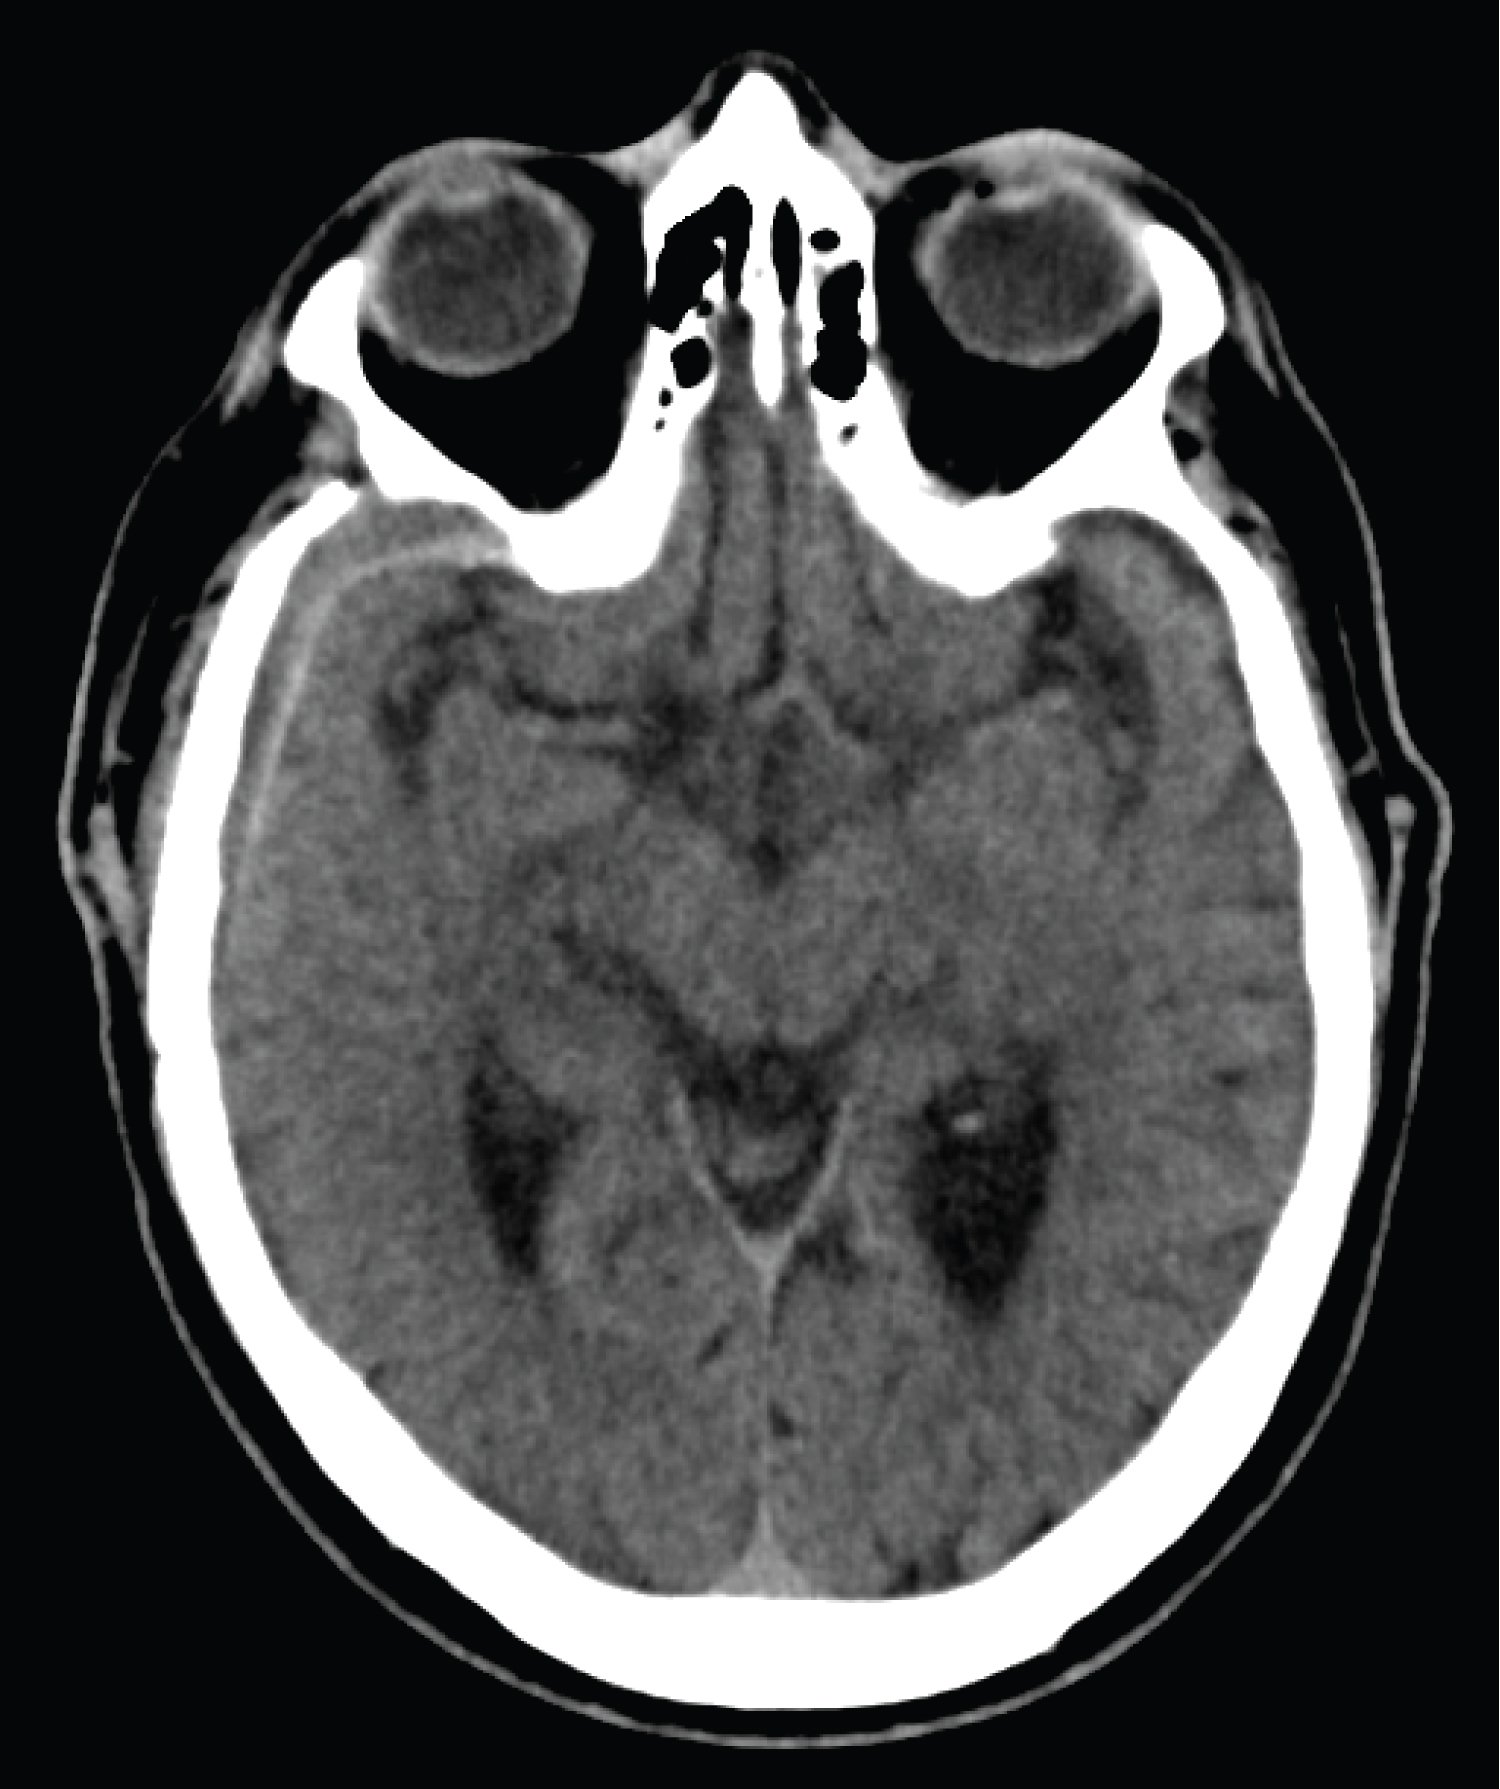

A 53-year-old male inmate sustained a transorbital penetrating injury with a ballpoint pen, and a transmaxillary penetrating wound injury with a pencil. He was transferred to our university hospital fully alert, with stable vital signs, and GCS score of 13 (E3, V4, M6). On presentation, only the pen cap was visible, extending outward from his right medial canthal fold (Figure 1). Physical exam demonstrated right sided ophthalmoplegia, with absent pupillary responses to both direct and consensual light, and loss of light perception in the right eye. Left sided extraocular movements remained intact, and the left pupil was reactive to direct but not consensual light. His neurological exam was otherwise, normal. A computed tomography angiography (CTA) scan of the head demonstrated the pen entering the right medial orbit, extending intracranially through the superior orbital fissure along the lateral wall of the right cavernous sinus, and terminating supratentorially in the right temporal lobe (Figure 2A and Figure 2B). There was no evidence of hemorrhage along the track, and the right internal carotid artery was separated from the pen by two millimeters. A second tubular foreign body was seen beginning at the anterior aspect of the left masseter muscle, entering the lateral wall of the left maxillary sinus, and then passing through the medial wall of the sinus, inferior turbinate, nasal septum, and right ostiomeatal complex before terminating in the inferolateral right orbital wall (Figure 2C).

Figure 2: (A,B,C) Brain and Bone window axial and coronal CT scans demonstrating ball point pen and pencil trajectory. View Figure 2